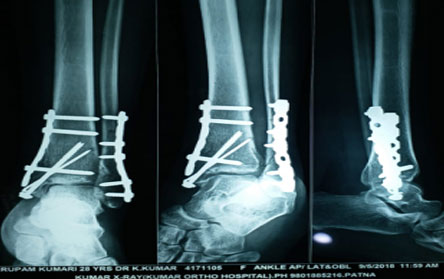

The Center of Orthopedics KUMAR ORTHO HOSPITAL ,Patna, offers the entire spectrum of modern orthopedic management, which is effective, patient - friendly & result oriented. In a nutshell, it is one stop treatment for all orthopedic ailments and fractures with emphasis on avoidance of complications, rapid mobilization, decreased period of confinement and an early return to normalcy.